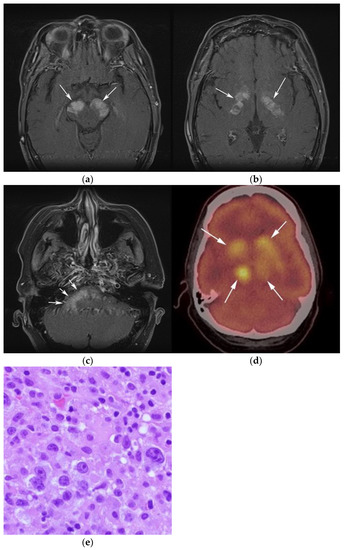

Figure 2.

A 64-year-old-woman presenting with rapid onset of memory deterioration and altered sensorium. (a) Coronal MRI T1 post-contrast images show subtle enhancement along bilateral deep nuclei. At this time, no diagnosis was determined. After 3 weeks, patient presented to emergency department with worsening symptoms. A follow-up MRI was performed. (b) Coronal MRI post-contrast fat-saturated images revealed progressive increase in extent of diffuse infiltrative enhancing masses (white arrows).

Figure 3.

Same MRI series. (a) Axial post-contrast MRI image shows lesions extending caudally to involve the bilateral superior cerebral peduncles and anterior aspect of the mid-brain. (b) Axial MRI T1 post-contrast fat-saturated images show involvement of the posterior limb of the internal capsule and the thalami bilaterally (white arrows). (c) Extension along the lateral aspect of the pons, dentate nucleus, and the middle cerebellar peduncles (white arrows). (d) Axial FDG fused PET/CT image shows increased activity in the aforementioned lesions. Additional hypermetabolic lesions are seen along the course of the corticospinal tract (white arrows). Imaging findings and pattern of involvement are consistent with lymphomatosis cerebri. (e) H&E section shows a tumor composed of large and pleomorphic cells with intermingled small lymphocytes. Primacy CNS lymphoma typically demonstrates an angio-centric predilection. (Original magnification 400×, H&E stain). Other differential diagnoses include a vasculitic process, toxic or metabolic encephalopathy, paraneoplastic syndrome, or acute disseminated encephalomyelitis. Biopsy showed a large non-cohesive B-cell lymphocyte population consistent with LC.

Special sequences such as apparent diffusion coefficient (ADC) maps help differentiate PCNSL from high-grade tumors such as glioblastoma multiforme (GBM). PCNSL demonstrates marked diffusion restriction on diffusion-weighted images (DWI) with lower ADC values compared to GBM due to tumor restriction in lymphoma cells. The main role of 18F-FDG PET/CT in CNS lymphoma is to differentiate PCNSL vs. disseminated systemic lymphoma involving the CNS [14]. Additionally, 18F-FDG PET/CT can help in distinguishing PCNSL from mimicking disorders such as hypometabolic intracranial opportunistic infections including CNS toxoplasmosis [15,16,17,18]. Imaging findings of LC include diffuse, non-mass-like lesions within both hemispheres involving the white matter, corticospinal tracts (CST), and deep gray matter. These lesions show patchy contrast enhancement and diffuse abnormal T2W hyperintensity. Unlike PCNSL, LC shows variable restriction on DWI [19]. Regions commonly affected in LC include the subcortical, deep, and periventricular white matter, CST, U-fibers, corpus callosum, and gray matter, with less frequent involvement of the spinal cord compared to PCNSL [12]. Contiguous spread of lesions from the cerebral white matter to the brain stem along the corticospinal tract (CST) is a notable feature of LC, which can involve both the brain and brain stem (Figure 2 and Figure 3). Unlike PCNSL, the characteristic neuroradiological findings of LC with 18F-FDG PET/CT have not yet been established; nevertheless, they are usually seen as hypermetabolic mass like lesions [8,20]. MRI spectroscopy (MRS) may help differentiate LC from other neurodegenerative or inflammatory conditions. On MRS, evidence of high cell membrane turnover (high choline peak), neuronal damage (decreased NAA levels), high lactate levels, and elevated lipids is typically demonstrated. Although many of these MRS features resemble high-grade gliomas and metastases, elevated lipids have been shown to be potentially useful to differentiate between these entities and LC [21]. The diagnosis of lymphomatosis cerebri should be considered in patients presenting with a rapidly progressive decline in cognitive function, dementia, or behavioral abnormalities. Imaging findings including diffuse bilateral hemispheric cortical spinal tract involvement and pathology may show predominant infiltration of the neuronal tracts without the formation of definite masses. It is crucial that diagnosis of LC is only made after the exclusion of other common etiologies as the clinical and imaging findings of LC can be misattributed to other diffuse infiltrative brain tumors, leukoencephalopathy, vasculopathy, degenerative disease, ischemic processes, infectious processes, and toxic demyelinating diseases in addition to dementias and other psychiatric disorders such as depression [8,12].